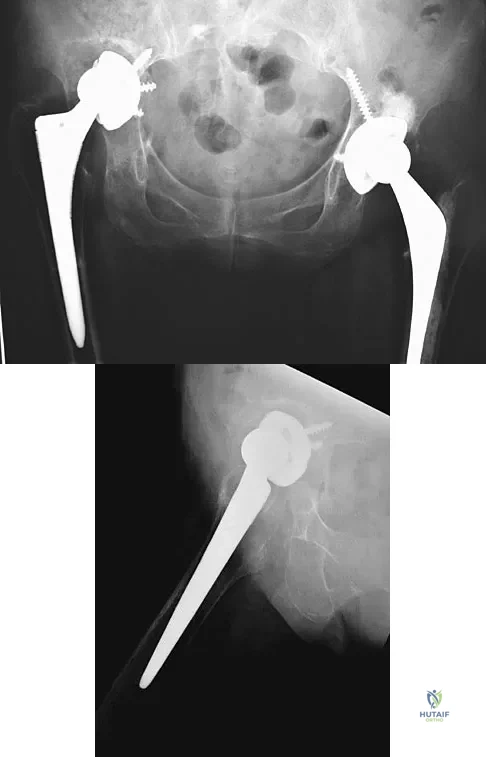

Question 95

A 32-year-old man has posttraumatic arthritis after undergoing open reduction and internal fixation of a left acetabular fracture. A total hip arthroplasty is performed, and the radiograph is shown in Figure 18. What is the most common mode of failure leading to revision in this group of patients?

Explanation